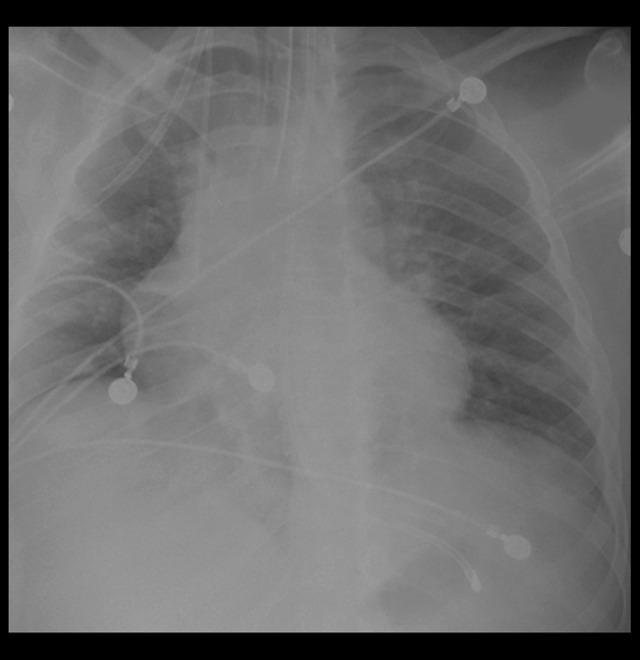

BACKGROUND In early 2020, severe acute respiratory syndrome-corona virus 2 caused an outbreak of a viral pneumonia that rapidly progressed to a global pandemic. Most cases presented with mild respiratory symptoms and required only supportive care with instructions to self-quarantine at home. Others had more severe symptoms that became complicated by acute respiratory distress syndrome (ARDS) and required hospitalization. CASE REPORT In this report, we present the case of a young patient in New York City who presented to our hospital with coronavirus disease 2019-induced diabetic ketoacidosis (DKA) that progressed to ARDS and subsequent death. The patient was managed for DKA on presentation with insulin protocol and acidosis management. However, it became evident that he had underlying respiratory complications, which later presented as ARDS requiring mechanical ventilation and antibiotics. CONCLUSIONS We recommend that clinicians be aware of this potentially fatal complication in all patients with pre-existing diabetes. Simultaneously, a low threshold for intubation should be advocated for patients with concurrent COVID-19 and type I diabetes mellitus since the potential for poor clinical outcomes from respiratory demise may be lessened by early respiratory intervention.

背景 2020 年初,严重急性呼吸综合征冠状病毒 2 引发了一场病毒性肺炎疫情,并迅速演变成全球大流行。大多数病例表现为轻度呼吸道症状,仅需给予支持性治疗并指示在家自我隔离。其他病例则出现更严重的症状,并因急性呼吸窘迫综合征(ARDS)而复杂化,需要住院治疗。病例报告 在本报告中,我们介绍了一名纽约市的年轻患者,该患者因 2019 冠状病毒病诱发糖尿病酮症酸中毒(DKA),进而发展为 ARDS 并最终死亡。患者就诊时按照胰岛素方案和酸中毒管理措施对 DKA 进行治疗。然而,很明显他存在潜在的呼吸道并发症,后来表现为需要机械通气和使用抗生素的 ARDS。结论 我们建议临床医生对所有患有糖尿病的患者都要意识到这种潜在的致命并发症。同时,对于合并 COVID-19 和 1 型糖尿病的患者,应提倡较低的插管阈值,因为早期呼吸干预可能会降低因呼吸衰竭导致不良临床结局的可能性。